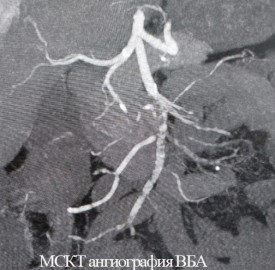

В НМИЦ им. В. А. Алмазова врачи смогли предположить такой диагноз, который подтвердился в обоих случаях после срочного выполнения анализов и компьютерной томографии. Получив результаты обследований, эндоваскулярные хирурги и врачи отделения хирургических методов лечения онкологических больных приняли совместное решение о необходимости экстренной операции.

Обеим женщинам было выполнено эндоваскулярное вмешательство — без разрезов, через прокол в бедренную артерию в паху был введен зонд, с помощью которого врачи удалили тромбы из просветов сосудов. Обе пациентки были в сознании во время операции, и прямо на операционном столе у них прошел болевой синдром.